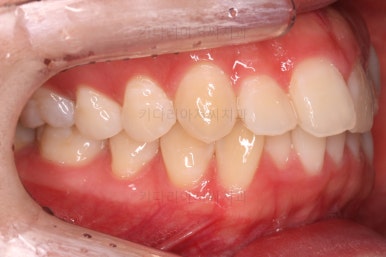

1. 초진

초진 시 입안의 모습입니다.

전반적으로 치열이 삐뚤고요.

위아래 중앙선이 약간 틀어져 있는데 많이 심한 편은 아니고요. 윗니가 배열된 U자 형태를 보면 아랫니보다 좁은 형태로 "악궁이 좁은" 상황이었습니다.